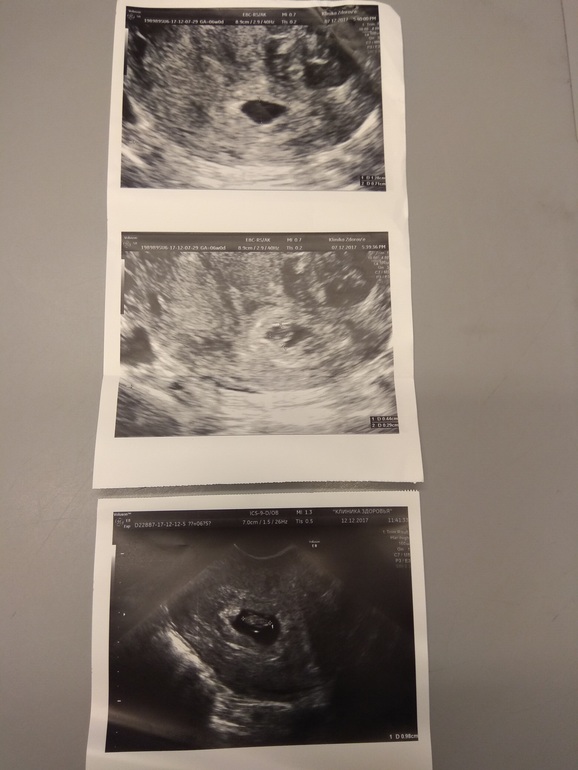

первая картинка-последнее узи последняя картинка-первое узи средняя картинка-оба УЗИ: первое УЗИ (вверху) и второе УЗИ (внизу)

Поняла) Лен,у тебя ПЯ на узи от 12.12 прям хорошее, ттт. И эмбриончику там прям свободно. Замер яйца не совсем мне кажется корректный был. Или действительно, свд замерили - средний внутренний диаметр. А если отрезком мерять - то по длине ПЯ точно мм 20, а то и более даже. Я боялась, вдруг эмбрион быстрее яйца растет и как бы тесно там, но даже по фото этого нет. Расслабляйся и выдыхай давай! По узи хорошо у тебя, и по размерам догоните!